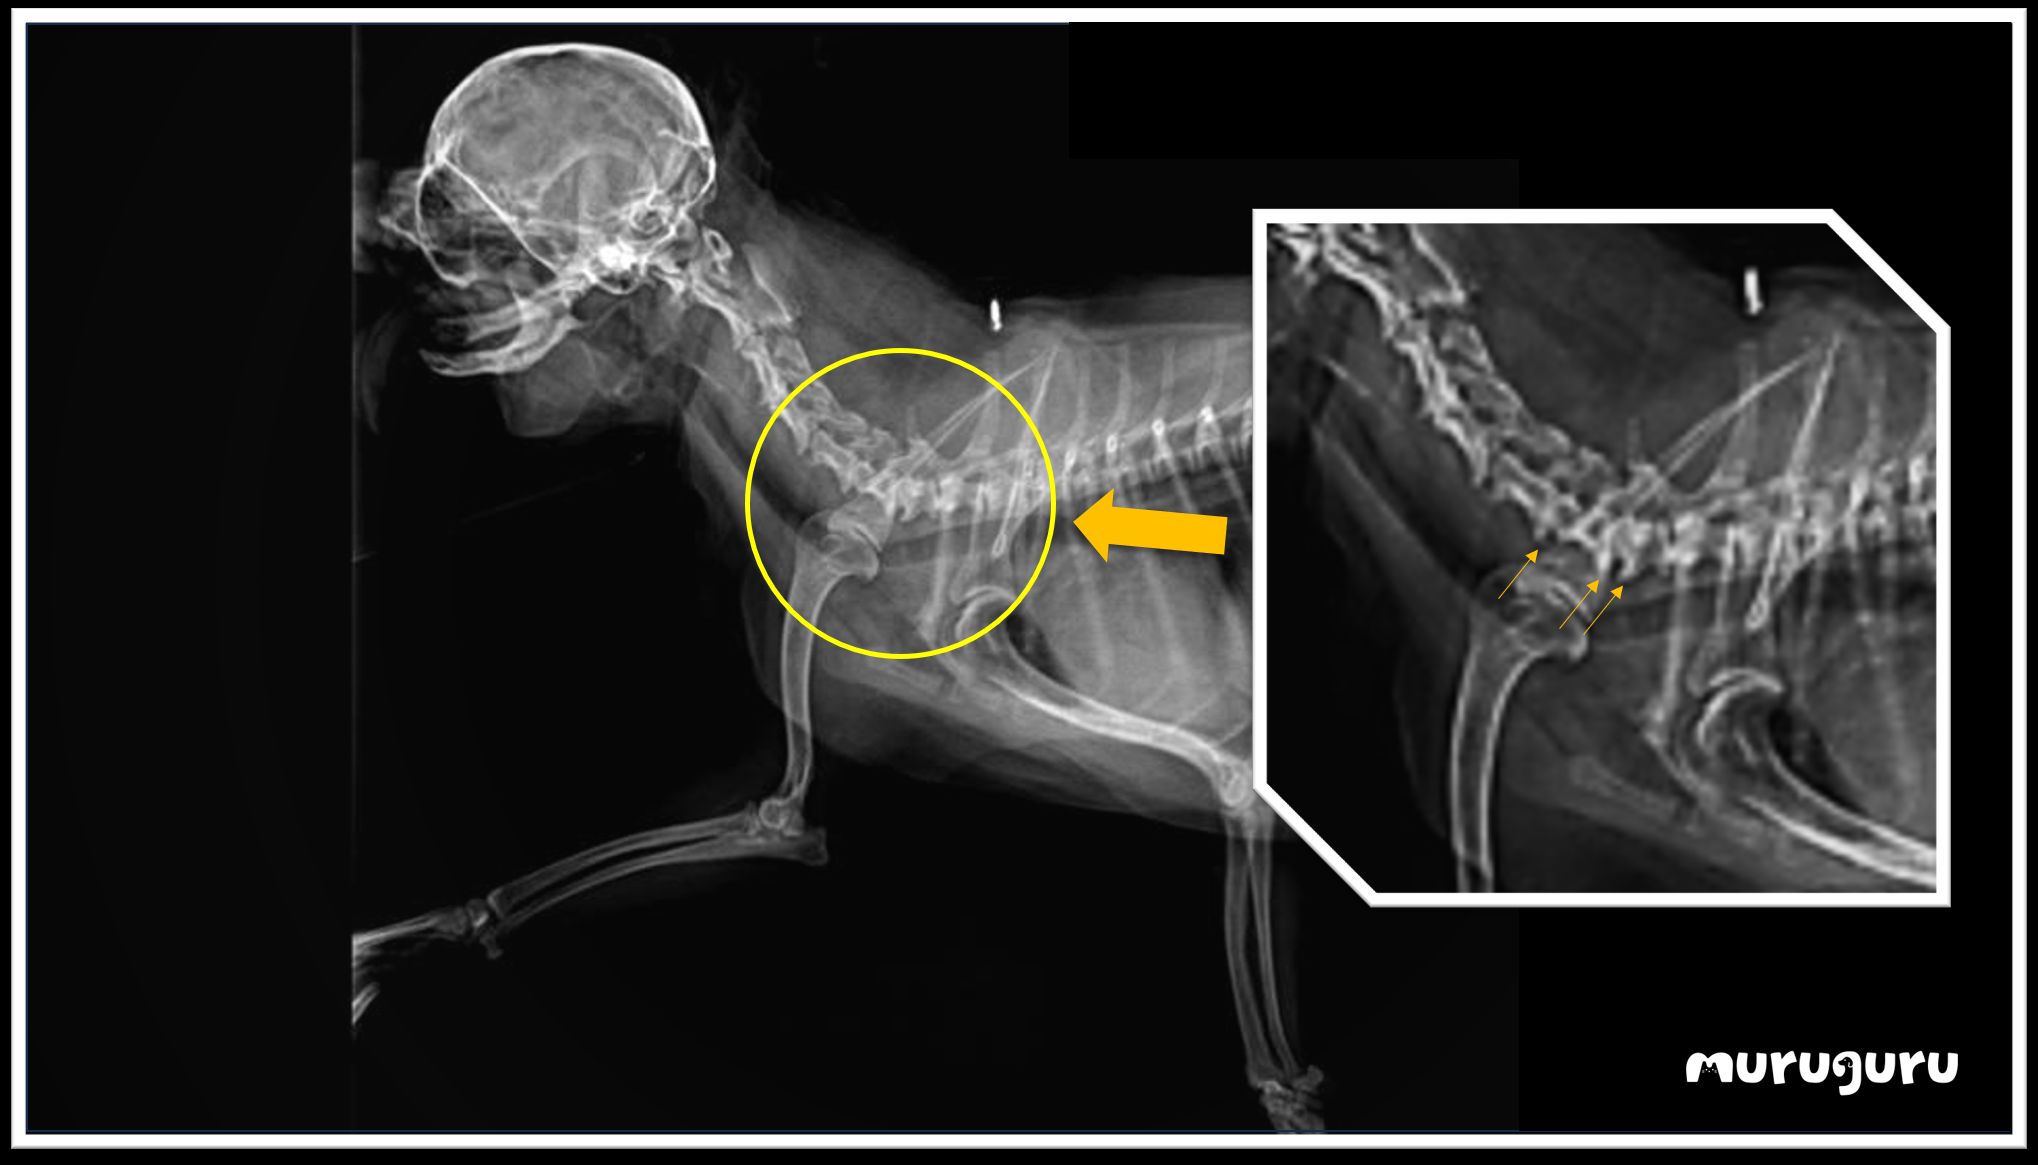

在老年貓狗中,骨刺是一種相當常見的毛病,通常在兩塊骨骼的交界處出現骨質增生。根據X光影像,波波的第五至七節頸椎出現了微小的骨刺,雖然數量不多,但突出來壓迫了傳遞去右手的神經線,對神經傳遞造成影響,結果右手失去了神經反射,導致癱瘓的情況發生。